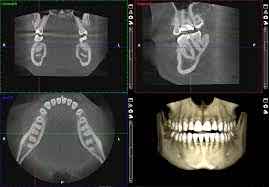

Full-arch is at the core of what we do. Our end-to-end All-on-X workflow covers everything from digital planning and surgical guides to conversions and final restorations — all in one streamlined, lab-friendly system. Designed for scale, built for precision, and trusted across thousands of cases.